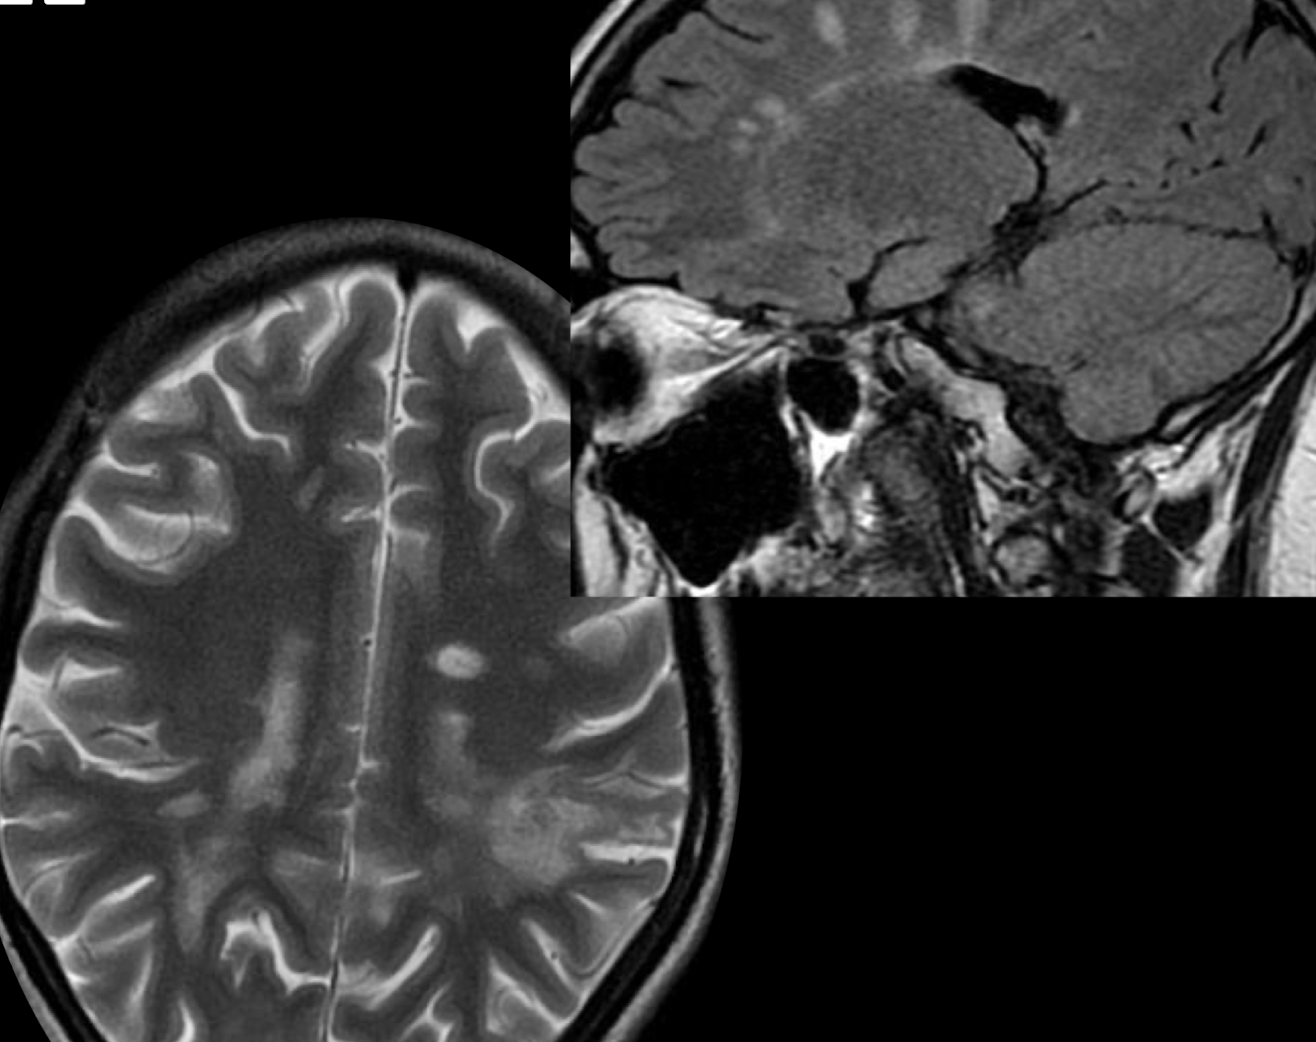

RM que vemos

Hiperintensidades calloseptales en T2 y flair

Pequeñas 5-10 mm, lineales y ovoides

Dedos de Dawson periventriculares